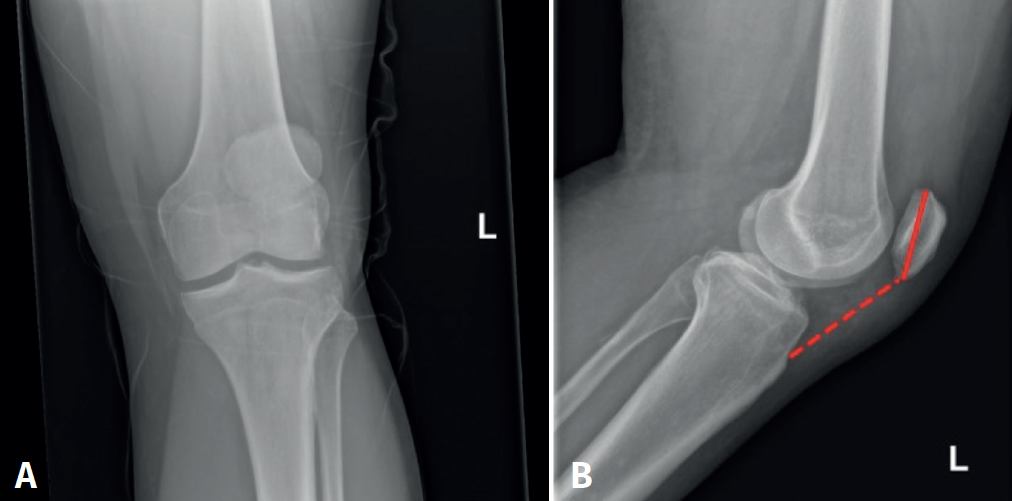

A 44-year-old male with no relevant disease history presented due to persistent functional impotency of the left knee following direct low-energy trauma to the joint three weeks ago. Exploration evidenced swelling of the pre-patellar region, with impossibility of extending the knee against gravity, and with the axe-stroke sign in the middle third of the patellar tendon. The anteroposterior and lateral radiographs of the knee evidenced a high patella (Figure 1).